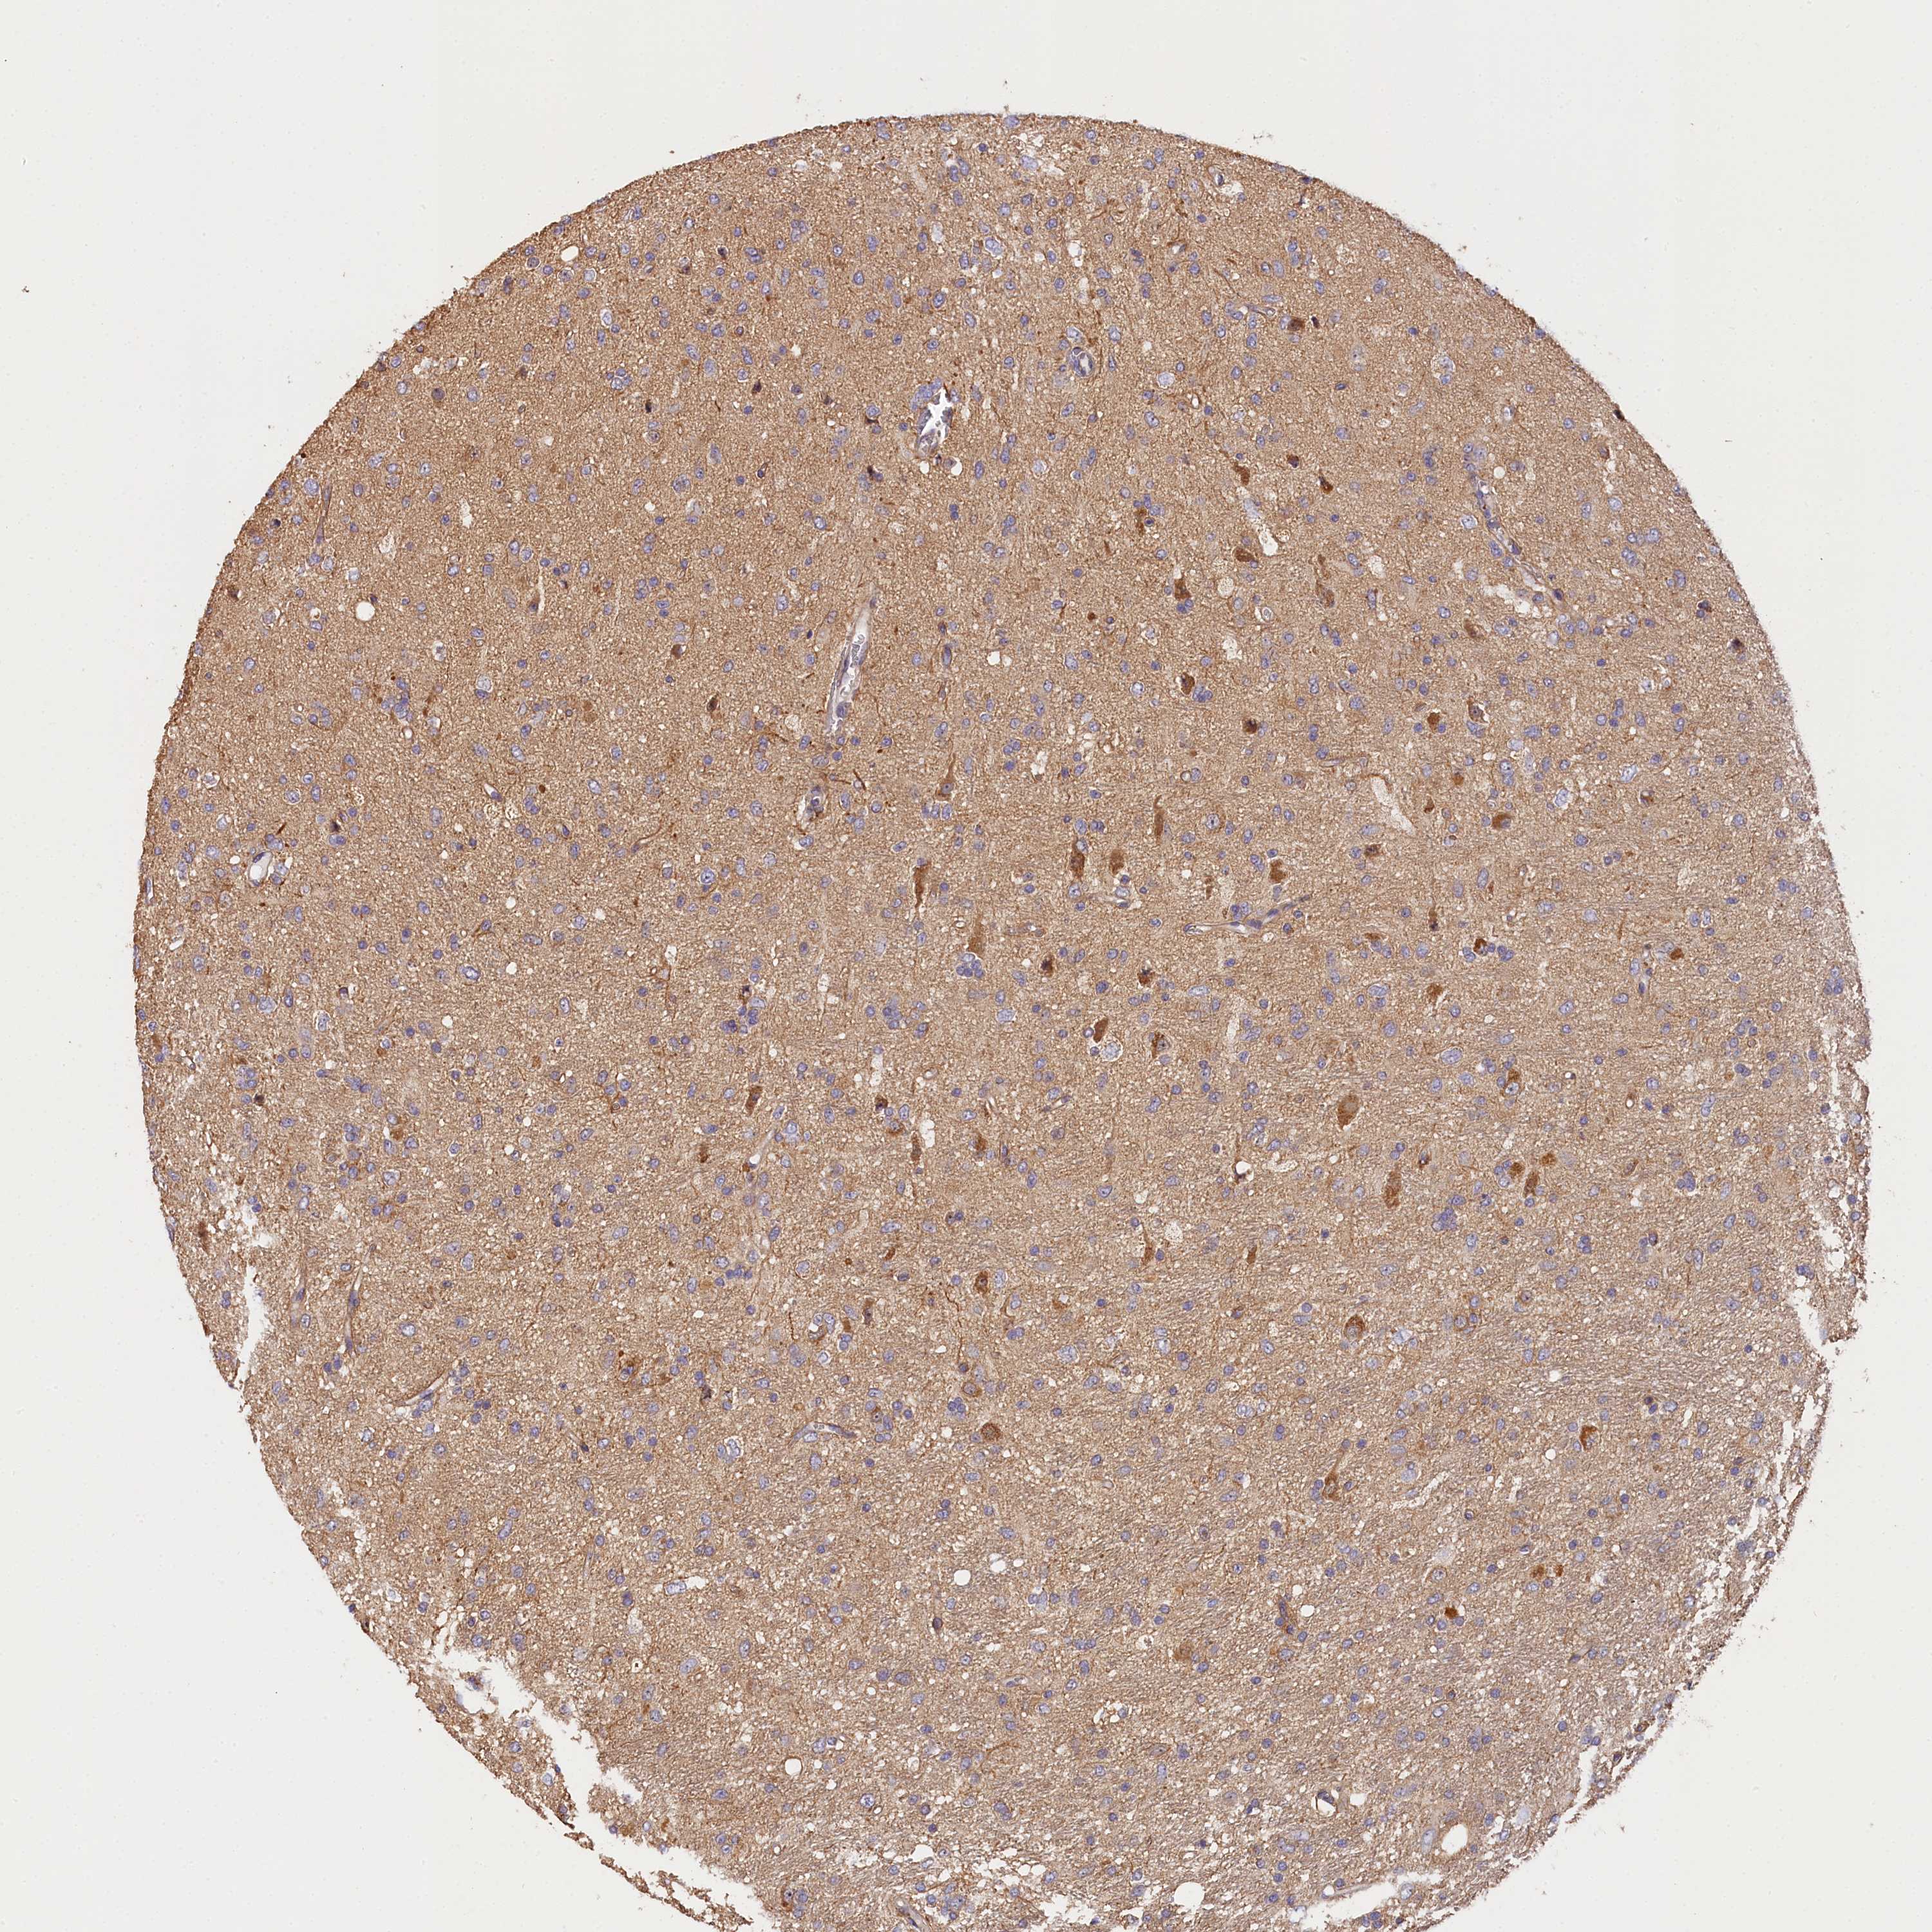

GLIOMA - Protein expressioni

A mouse-over function shows sample information and annotation data. Click on an image to view it in a full screen mode. Samples can be filtered based on level of antibody staining by selecting one or several of the following categories: high, medium, low and not detected. The assay and annotation is described here.

Note that samples used for immunohistochemistry by the Human Protein Atlas do not correspond to samples in the TCGA dataset.

Antibody stainingi

Antibody staining in the annotated cell types in the current human tissue is reported as not detected, low, medium, or high, based on conventional immunohistochemistry profiling in selected tissues. This score is based on the combination of the staining intensity and fraction of stained cells.

Each image is clickable and will lead to virtual microscopy that enables deeper exploration of all samples and also displays staining intensity scores, fraction scores and subcellular localization as well as patient and tissue information for each sample.

Antibody HPA041165

Antibody HPA041839

Staining

High

Medium

Low

Not detected

Intensity

Strong

Moderate

Weak

Negative

Quantity

>75%

75%-25%

<25%

None

Location

Nuclear

Cytoplasmic/membranous

Cytoplasmic/membranous,nuclear

Glioma, malignant, High grade

Glioma, malignant, Low grade